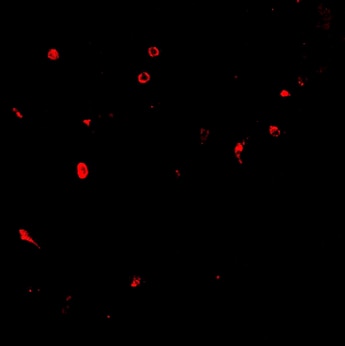

Immunohistochemistry E-Selectin/CD62E antibody in LPS treated Human Kidney Tissue. View Larger

E-Selectin/CD62E in LPS treated Human Kidney Tissue. E-Selectin/CD62E was detected in acetone fixed cryosections of human kidney tissue using Goat Anti-Human E-Selectin/CD62E Polyclonal Antibody (Catalog # BBA18) overnight at 4 ° C. Tissues were stained with rabbit anti-goat secondary antibody and HRP polymer-conjugated anti-rabbit IgG followed by AEC+Substrate Chromogen (red) followed by counterstaining with hematoxylin (blue). Before incubation with the primary antibody, tissues were treatedex vivowith LPS and also treated to block endogenous peroxidase activity. The lower panel shows an absence of labeling when primary antibody is omitted. Experiments were carried out and images were provided by Dr. Grietje Molema, University of Groningen, The Netherlands.